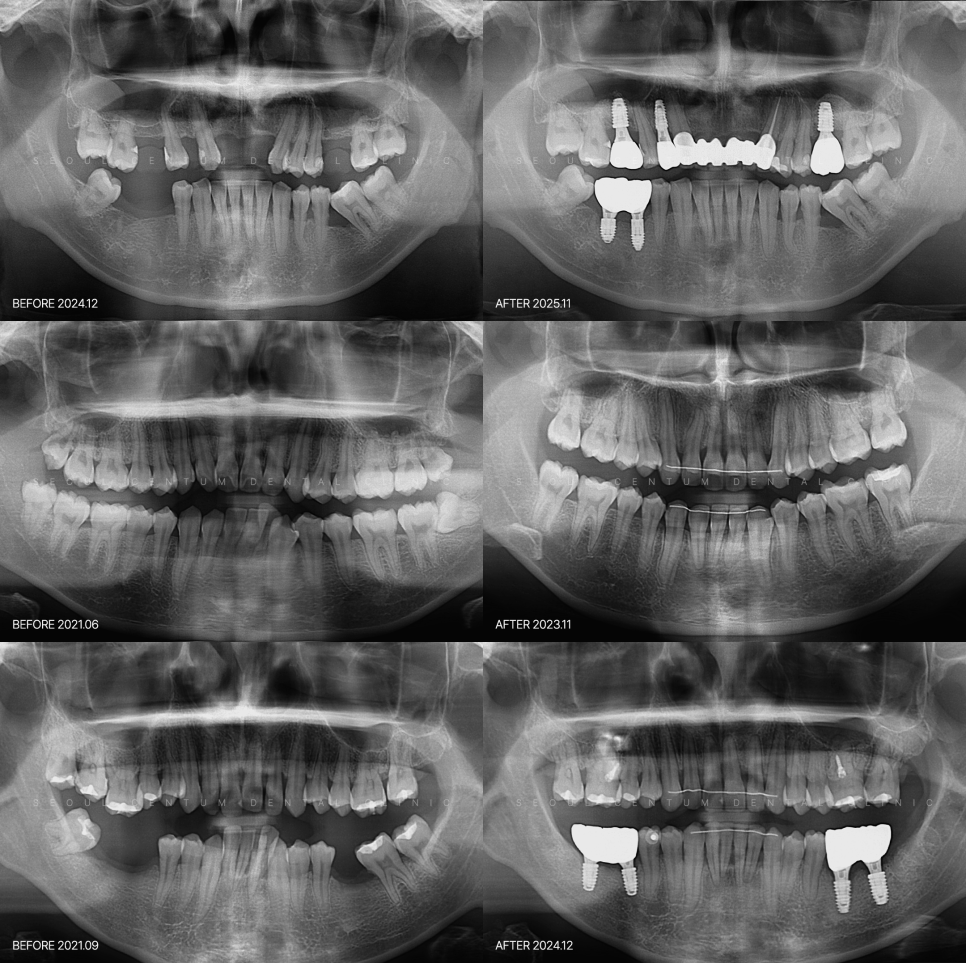

구강 문제는 생각보다 쥐도 새도 모르게 진행됩니다

충치나 잇몸 질환 초기에는

통증 없이 진행되는 경우가 많기에

어느 날 치아에 생긴 충치를 보고 놀라

찾아오시는 경우가 꽤 많습니다.

오래된 보철물 아래서 충치가 또 생기거나

잇몸뼈 흡수 같은 변화는

눈으로 확인하기 어렵고

증상을 느끼지 못하는 경우도 있어요.